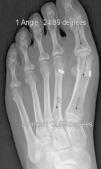

At this point, capsular plicature is performed in the traditional manner and the incisions are closed; the post-operative corrective bandages are as important as in percutaneous surgery. An orthopaedic shoe with an inverted heel is recommended and weight-bearing is not allowed for 2 weeks, at which time the sutures are removed and partial, gradual weight-bearing is begun starting at week 3. Patients can normally wear a non-orthopaedic shoe starting in week 6, at which time full weight-bearing is started (Figs. 1 and 2).

The 36 feet treated with this technique were evaluated and improvement of the IMA was achieved from 13.8° (range: 11–16°) to 7.6° in the immediate post-operative (range: 7–10°) with a mean improvement of this parameter of 6.2° (p<0.01). The HVA improved from a mean pre-operative value of 26.8° (range: 19–34°) to a mean value in the immediate post-operative period of 13.7° (range: 12–20°), showing a mean improvement of 13.1° (p<0.05). The results obtained at 15 days did not differ from the initial outcomes, although the results obtained starting at week 6 did improve, when the mean post-operative IMA was 8.6° and the HVA, 15.2°, with mean losses of 1° and 1.5°, respectively, in reduction. The values obtained at 3 months reveal a mean IMA of 9° and HVA of 16.2°, i.e. a loss of 1.4° in correction with respect to the initial IMA and 3.5° insofar as the initial HVA is concerned. At the 6-month, 1-year, and final follow-up visits, there were no variations as regards the IMA, but the HVA at the 1-year follow-up was 16.8° (Table 1). Therefore, there was an overall improvement at the final follow-up visit of 4.8° in the IMA (p<0.05), having lost 22% of the initial gain, and 10° in the HVA (p<0.05), having lost 27% of the initial gain (Table 2).

In our opinion, optimal radiological correction can be defined in terms of the initial classification (obtaining angle values within normal limits, namely IMA < 9° and HVA <11°) or in statistical terms (significant differences with a p value of at least <0.05). Insofar as the correction values obtained in this study are concerned, they demonstrate that this system makes it possible to achieve adequate correction of the IMA (both statistically and in “ideal” terms) and of the HVA (more statistical than classification, given that we manage to lessen the severity, albeit not bringing it back to normality, strictly speaking), comparable to other series that have made use of classical techniques34–36 (Table 1), although the immediate follow-up (up to 3 months) saw a 20% loss in the correction initially gained with the surgery. This does not increase over the subsequent follow-up visits and in no case has caused symptoms that have necessitated re-intervention for this reason (Figs. 3 and 4). In the same regard, if re-intervention is necessary because an osteotomy on the first metatarsal had not been performed, this would enable us to perform the pertinent technique without the problem of working on bone that has already been osteotomized.